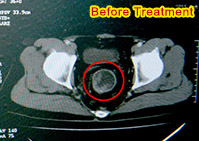

Non-surgery Treatment Helped Return My Life bHATTA from Indonesia, a rectal cancer patient, underwent interventional therapy, natural therapy, and other comprehensive therapies in Modern Cancer Hospital Guangzhou. The symptom of bloody stool was removed and the tumor also disappeared.[Read more]

Umar Latinulu: Thank MCHG for Being There on After receving interventional therapy and natural therapy provided by MCHG, Umar Latinulu’s colon cancer tumor shrunk by 95% and he also gained some weight. His work and life now has basically returned to normal. [Read more]

I Choose It Because of My Trustas knowing friends who had tumor got effective treatment in Modern Cancer Hospital Guangzhou, I chosen to go here too and got good efficacy. Within less than 6 months, CT scan showed there was no tumor in my body anymore![Read more]